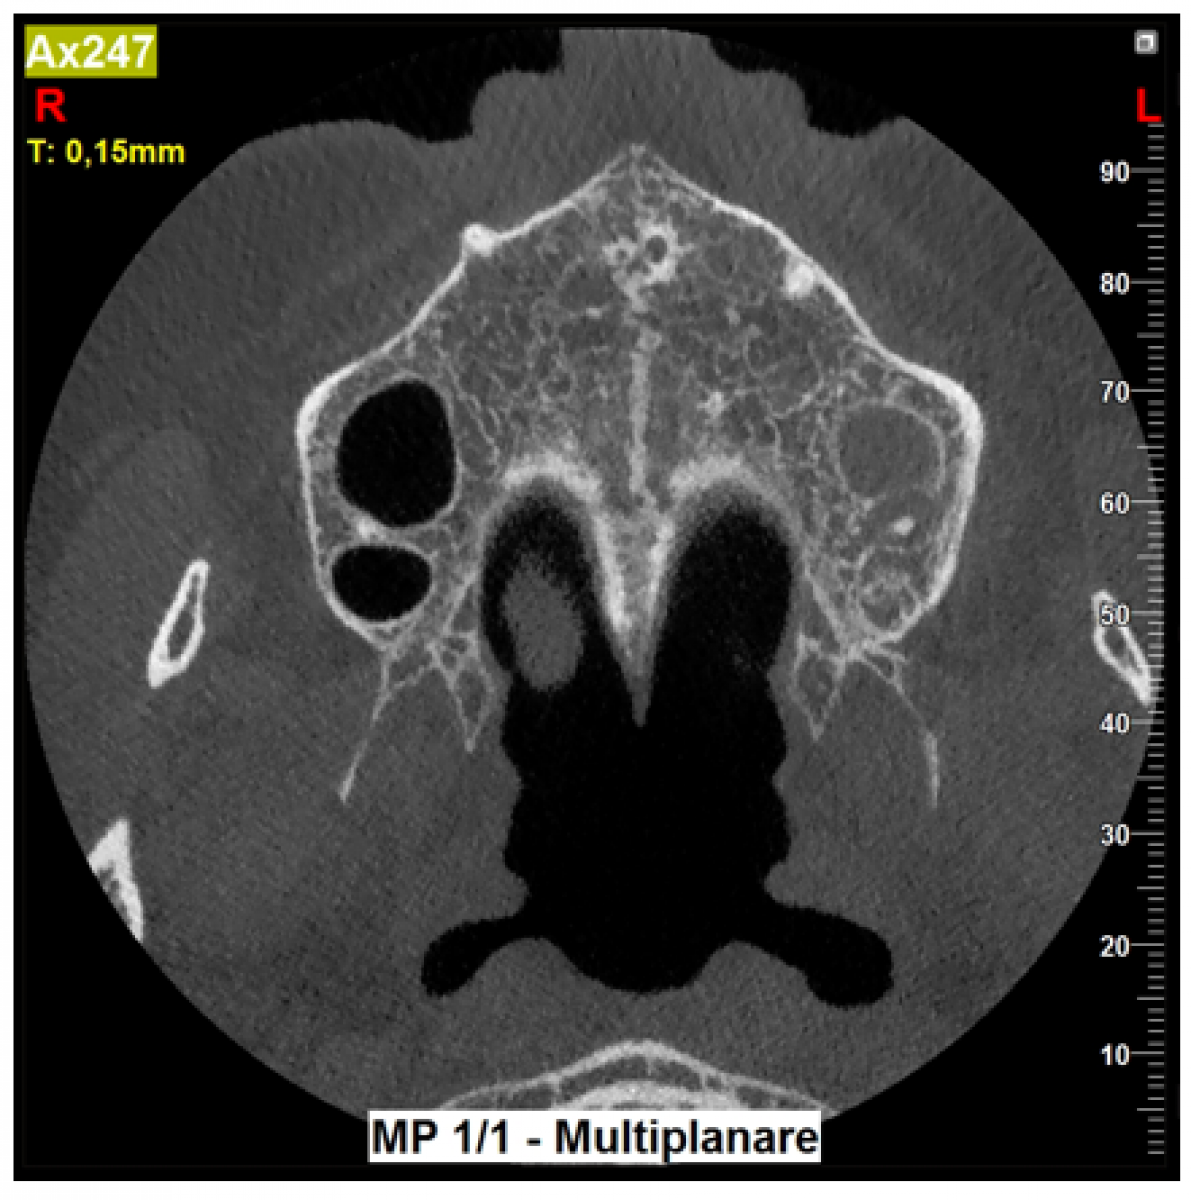

Upon re-evaluation after one month, the patient reports that she has not benefited from the therapy, persisting the symptoms that have even spread to the subzygomatic area. Furthermore, even at the periodontal examination, the probing has not decreased despite sufficient plaque control. . It was then decided to proceed with a second level X-ray examination justified by the diagnostic insufficiency of a two-dimensional X-ray. Accordingly, we opt for an 8x6 FOV with a "Regular" program to bilaterally investigate the maxillary sinuses and the entire maxillary arch to search for periradicular bone resorption.

The CBCT performed showed a patent and well-ventilated right maxillary sinus. In contrast, the left maxillary sinus was full of beacon material compatible with the presence of an infectious-inflammatory pathology. In addition, the sagittal cuts made it possible to highlight the presence of a bucco-sinus communication at the level of element 2.7, the cause of the patient's symptoms. In particular, the communication has created a path that runs along the buccal surface of the tooth in question. At this point, the case will be managed in an interdisciplinary way together with the otolaryngologist colleague.